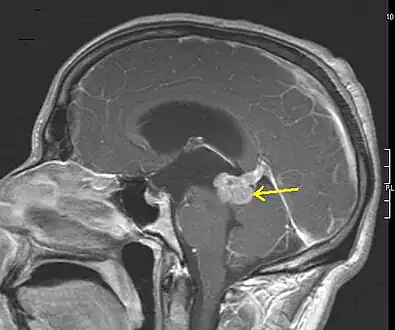

Low grade astrocytoma of the midbrain (lamina tecti), sagittal T1-weighted magnetic resonance imaging after contrast medium administration: The tumor is marked with an arrow. The CSF spaces in front of the tumor are expanded due to compression-induced hydrocephalus internus.